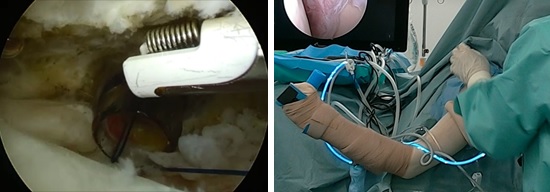

鏡視下滑膜切除(クリーニング手術)

肩関節鏡視下に痛みの原因となっている充血した滑膜を可及的に切除します。

- 手術日:1時間程度の鏡視下手術になります